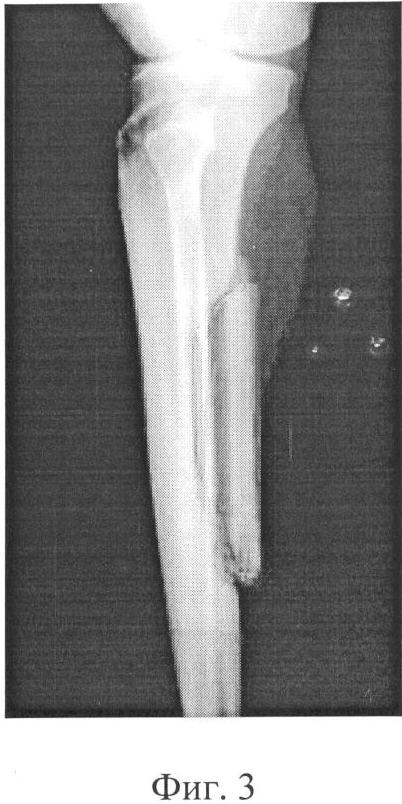

Фиг.3 – рентгенограмма больного после лечения.

В результате проведенного лечения у больного улучшилось состояние кровоснабжения дистальных отделов правой нижней конечности, что нашло выражение в потеплении кожных покровов, нормализации их окраски, в увеличении продолжительности безболезненной ходьбы.